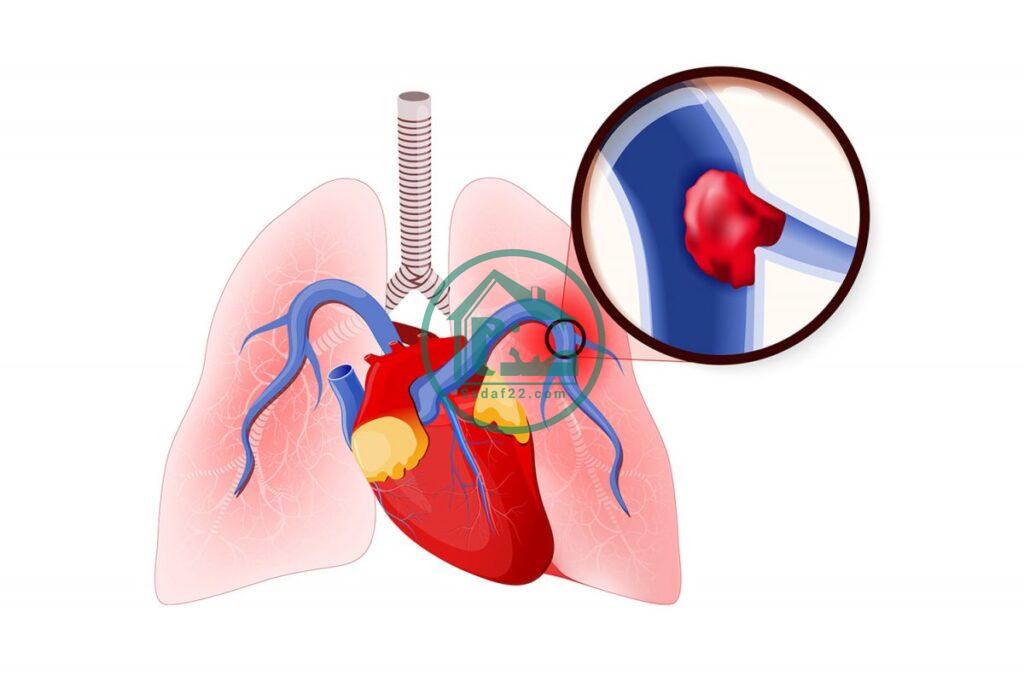

حمید عمادی، متخصص بیماریهای عفونی و گرمسیری با بیان اینکه آمبولی ریه به اثر لخته شدن خون در ریه و آسیب به عملکرد این اندام گفته میشود، اظهار کرد: ویروس کرونا تاثیر شدیدی بر بدن و ریه می گذارد و در نهایت کاهش اکسیژن باعث اختلال در عملکرد و التهاب ریه خواهد شد، در واقع ویروس کرونا بر فرآیند ایجاد آمبولی موثر است.

عمادی با بیان اینکه عروق یا رگها هم تحت تاثیر التهاب ریوی قرار میگیرند، تاکید کرد: از آن جایی که در فرد مبتلا به کرونا التهاب شدید ریوی یا عروقی ایجاد میشود و تمامی رگها ملتهب میشوند در نهایت احتمال بروز لخته در عروق زیاد میشود و این لختهها با گیر کردن در مغز و قلب بروز سکته مغزی و سکته قلبی را بسیار محتمل میکنند، همچنین میتوانند در رگهای موجود در ریه گیر کرده و آمبولی ریه ایجاد کنند.

متخصص بیماریهای عفونی و گرمسیری ادامه داد: به طور معمول بیماران کرونایی که دچار التهاب شدید ریوی شده اند و در بیمارستان بستری هستند با مصرف داروهای ضد انعقاد به منظور جلوگیری از لخته شدن خون شان تا حدودی درمان خواهند شد تا به اینصورت از ابتلای آنها به آمبولی ریه پیشگیری کنیم.

او گفت: آمبولی ریه و سکته قلبی و سکته مغزی میتواند منجر به مرگ افراد شود، اما با مصرف داروهای ضد انعقاد درمان میشوند البته در برخی موارد هم بیمار جان خود را از دست میدهد.

عمادی در پایان یادآوری کرد: با تشخیص زودهنگام افراد مبتلا به آمبولی ریه و مصرف متناسب دارو شانس بهبودی آنها افزایش پیدا میکند در غیر اینصورت احتمال مرگشان وجود دارد.